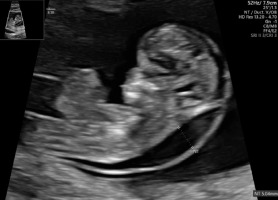

A thirty-three-year-old pregnant woman in her second pregnancy (the first pregnancy was unsuccessful – miscarriage at week 8 of pregnancy), visited a gynecologist for a routine check-up at week 12 of pregnancy, during which developmental disorders were found in the anterior chest cavity and abdominal walls. The woman was healthy, denied having chronic diseases, and was taking folic acid and vitamin preparations for pregnant women. The patient also denied the existence of any infections at an early stage of pregnancy. The woman was referred to the Laboratory of Prenatal Research, where, during prenatal ultrasound examination, the fetus was diagnosed with a complex defect of the skin and division of the body’s cavities in the form of pentalogy of Cantrell. The fetus was diagnosed with umbilical cord omphalocele (Figure 1), diaphragmatic hernia with diaphragmatic defect, sternal defect, ectopic heart and pericardial defect (Figures 2-3).